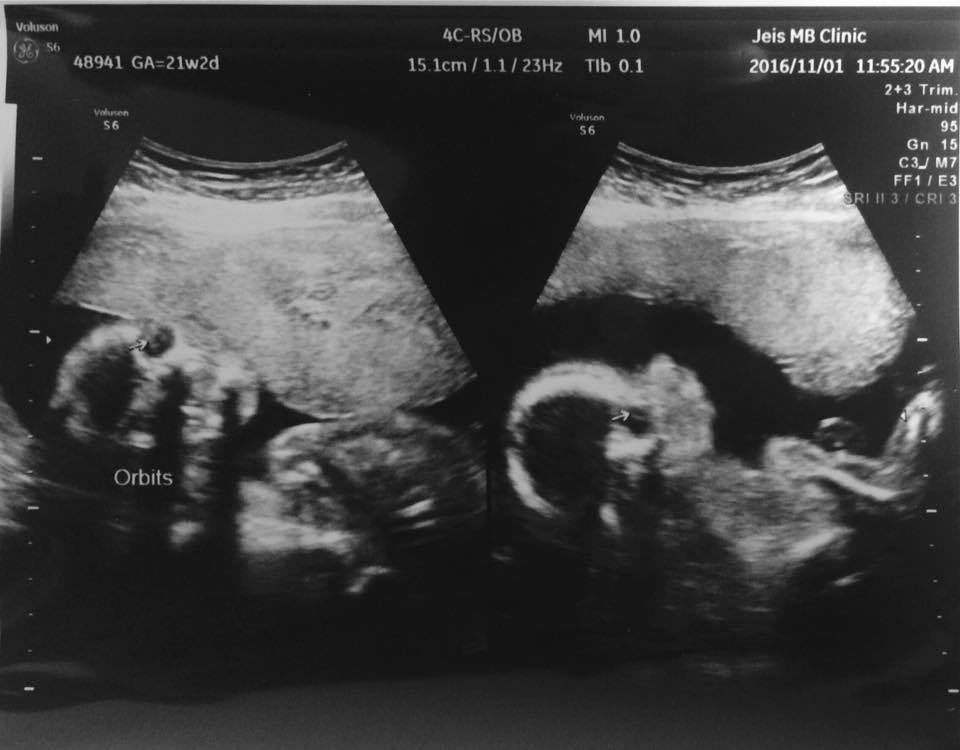

병원에선 초음파사진을 찍어주면서 "얘기가 참 이쁘네요." 하는데,

"눈이 참 예뻐요." 하는데,

아무리봐도, 잘모르겠다.

먼 흑백의 바다에 떠 있는 고래를 닮았다고,

아내는 말했다.